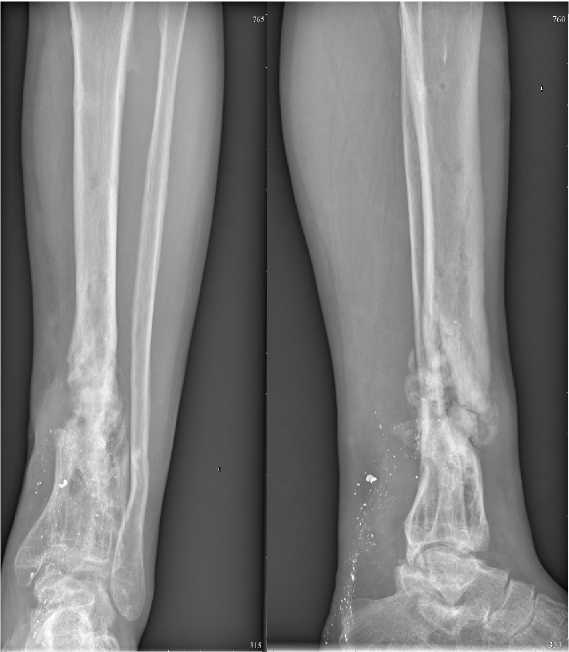

Рисунок 2. На рентгенограммах левой голени в двух проекциях определяются многооскольчатые переломы дистальных отделов костей голени с разнонаправленным смещением отломков, фиксированные аппаратом Илизарова

Figure 2. Radiographs of the left leg in two projections show multi-fragmentary fractures of the distal parts of the leg bones with multidirectional displacement of fragments, fixed with the Ilizarov apparatus